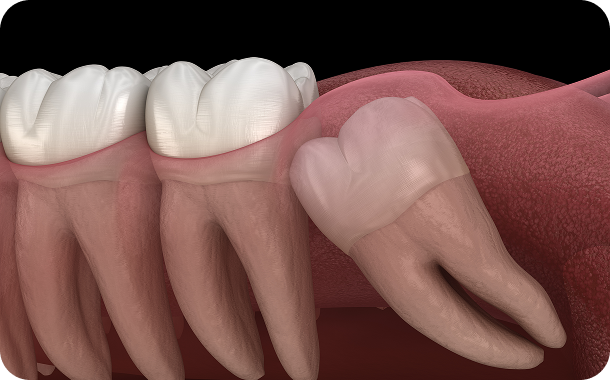

더블보드 전문의 설계는 다릅니다.

더블보드 전문의는 치아교정부터 고난도 치료까지 못하는 진료없이 다수의 임상 경험으로 만족도 높은 결과를 선사합니다.

연세아이돌치과교정과는 11년차 치과교정과 & 통합치의학과 더블보드 전문의가 직접 진료합니다.

단순한 치료를 넘어 일상의 완성을 설계하는

통합 진료 솔루션

단순한 치료를 넘어 환자의 마음을 헤아리는 것에서 연세아이돌치과의 진료는 시작됩니다.

치과교정과 전문의의 심미적 안목과 통합치의학과 전문의의 포괄적 진단이 만나는 곳.

연세아이돌치과교정과의 일반진료는 단순히 질환 부위만을 바라보지 않습니다.

치아 하나가 전체 구강 구조와 조화를 이루는지,

환자분의 식습관과 생활 패턴에 장기적으로 어떤 영향을 미칠지까지 치밀하게 계산합니다.